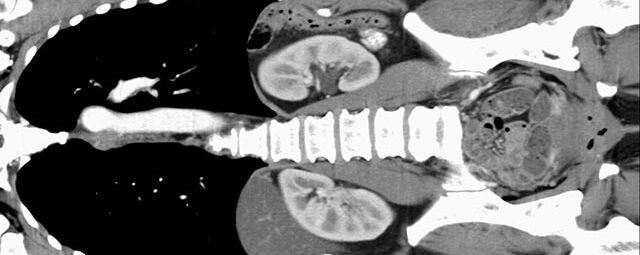

Abdomen (Bauch und Becken)

• Diagnostik von entzündlichen und tumorösen Erkrankungen der Bauchorgane

• Diagnostik von akuten Notfällen wie Darmverschluss, Hohlorganperforation oder Traumafolgen

• Darstellung der großen Gefäße zur Erkennung von Gefäßverschlüssen (z. B. Mesenterial - Arterienembolie oder Einengungen von Gefäßen (z. B. Nierenarterien)

• Darstellung und Therapieplanung von Aneurysmen (CT- Angiographie)

• Virtuelle Kolonographie zur Darstellung des Dickdarmes z. B. bei Kontraindikation zur Darm-Spiegelung oder nur unvollständig durchführbarer Koloskopie.